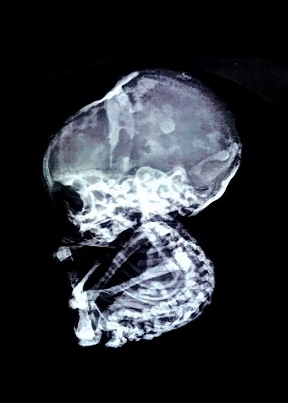

Vụ việc vừa khiến giới khoa học bất ngờ. Một người phụ nữ đã được cho biết có bào thai hóa đá trong bụng. Em bé hóa đá đã ở trong bụng mẹ 15 năm.

Người mẹ nói trên (xin được giữ kín danh tính) là một phụ nữ 52 tuổi sống tại một ngôi làng nhỏ gần Nagpur, ở bang Maharashtra, miền tây Ấn Độ.

Bà từng phải bỏ thai một lần cách đây 15 năm vì gia đình không thể cáng đáng thêm một đứa trẻ. Lúc đó, cả bác sĩ sản khoa và bác sĩ phụ khoa đều xác nhận đứa trẻ đã được loại bỏ thành công.

Thế nhưng, trong suốt nhiều năm qua, những cơn đau bụng dữ dội thường xuyên hành hạ người phụ nữ này, tới 3 năm gần đây, bà nôn ói liên tục. Những lần đi khám, bác sĩ đều chỉ cho thuốc giảm đau.

Cuối cùng, người phụ nữ tội nghiệp đã đến tìm tiến sĩ Nilesh Junankar, một chuyên gia sản khoa uy tín tại Ấn Độ. Và ông đã phát hiện tình trạng hiếm thấy khiến nhiều người không khỏi sửng sốt.

"Do tình trạng bất thường của bệnh nhân nên chúng tôi đã tiến hành nội soi và phát hiện ra một bất ngờ khủng khiếp. Một đứa trẻ 4 tháng tuổi trong bụng người mẹ này. Chúng tôi bị sốc. Điều này cực kỳ hiếm thấy" - tiến sĩ Junankar cho biết.

"Kinh nguyệt của bệnh nhân đã ngừng cách đây 5 năm và bà không ở trong độ tuổi sinh sản nên càng khó phát hiện hơn" - bác sĩ cho biết.

Các bác sĩ đã tiến hành phẫu thuật đưa đứa trẻ chết lưu đã "hóa đá" trong bụng người mẹ ra trong một cuộc phẫu thuật kéo dài 2 giờ hôm 23-11.

Khi thai được lấy ra, chính các bác sĩ cũng bị sốc vì kích thước của nó. Bào thai "hóa đá" đã gây tắc nghẽn đường ruột và chèn vào ống thực phẩm của người mẹ. Tuy nhiên, tử cung, buồng trứng và ống dẫn trứng vẫn hoàn toàn bình thường.

Mang thai "hóa đá" có tên khoa học là "Lithopedion", là một trong những hiện tượng cực cực kỳ hiếm gặp. Trên thế giới, tỉ lệ thai lưu hiện nay là khoảng 1/11.000 ca và chỉ có 1,5-1,8% trong số đó phát triển thành "Lithopedion".